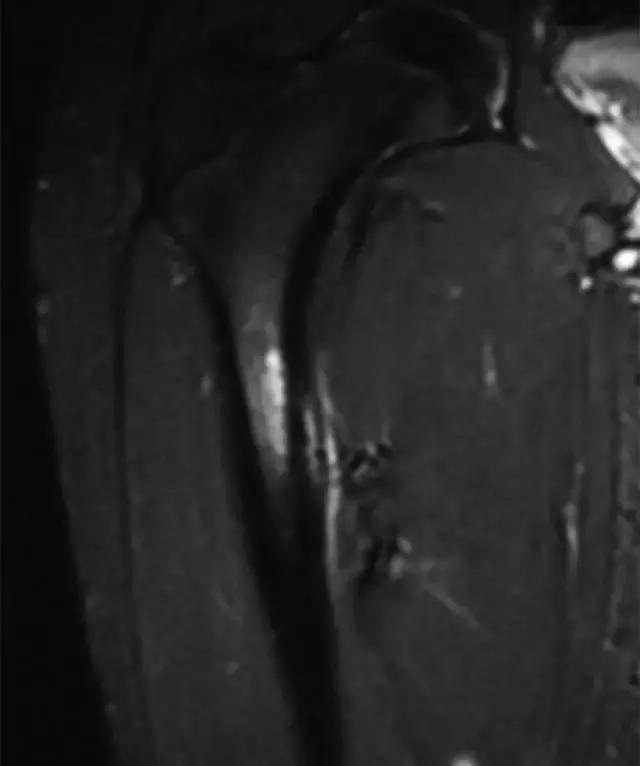

X光片可以揭示沿着股骨内侧轴上的骨膜反应,但研究结果往往正常(图12A)。 放射性核素骨扫描显示该区域的摄取增加,但MRI已成为评估该实体的首选研究[58]。 结果包括骨髓水肿和异常骨膜和皮层信号强度(图12B)。

图12A -14岁男子足球运动员,股骨应力骨折。右髋前后X线片显示沿内侧近端股骨轴的局灶性骨膜炎(箭头),仅在图像边缘部分可见。

图12B,冠状STIR MR图像显示广泛的骨膜反应,内皮和皮质内异常信号强度与发展中的应力骨折相适应。